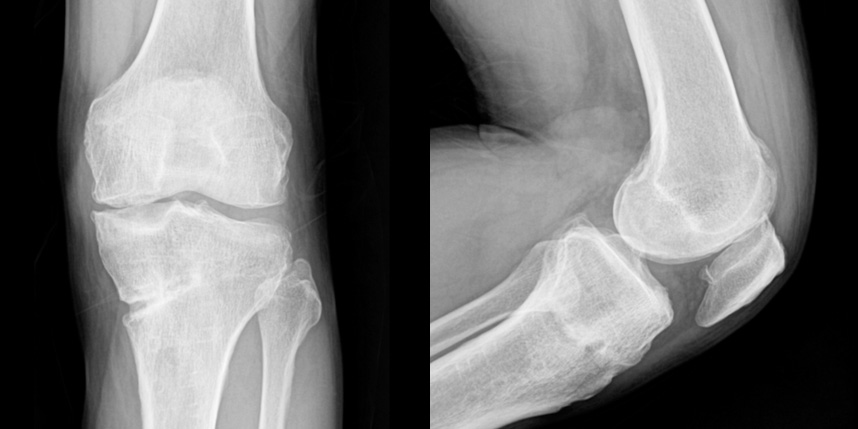

퇴행성 관절염으로 무릎 연골이 닳아 통증이 지속되는 환자

연골 손상으로 인해 치료받았으나 증상이 지속되는 환자

인공관절 치환술을 권유받았으나 이에 거부감이 있는 환자

관절 기능 회복 및

통증 완화

수술적 치료에 비해

비교적 간단하고

회복 기간이 짧음

인공관절 치환술을 지연시키거나 예방 가능